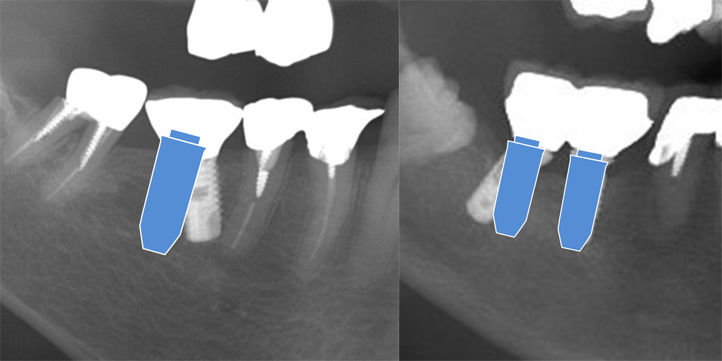

歯科医師から術前に提示された場所と違う位置、傾き、深さにインプラントが埋められるケースが多くみられます。

そのほとんどが術者の未熟さと3Dテクノロジー(ガイデットサージェリー)を応用せず、すべきステップを省いて行われたインプラント治療によるものです。

インプラント治療医 20名によるフリーハンドと3Dテクノロジーインプラントでの実際に埋入された部位との誤差比較した。

- フリーハンドで行ったインプラントでは容認できない位置、深さ、角度の誤差を生じていた。

- 術者によって、大きなバラつきが認められた。

- フリーハンド群の三次元的角度の誤差はガイド群に比較して3.2倍と高く、3Dテクノロジーによるガイドを用いることが正確なインプラント埋入には必須であると思われた。

以上のことから、歯科医師の経験と勘だけに頼ったインプラント治療は、より安全で確実なインプラント治療であるとは言えない。当院では「安心・安全・確実」なインプラント治療を提供する上で、フリーハンドではない、3Dテクノロジーインプラントを行い患者様のご要望にしっかりお応えします。